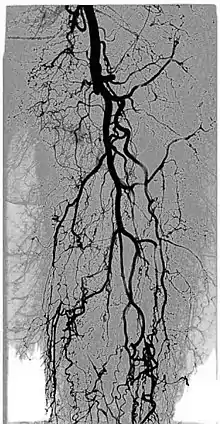

Kinetic image or DVA (digital variance angiography) of a patient's leg, obtained from previously acquired fluoroscopic angiography data. Movement of a bolus of contrast agent allows visualization of the blood vessels.

Digital variance angiography (DVA)

By allowing visualization of movements, kinetic imaging offers a new type of motion-based contrast. In many cases, the kinetic image will have a higher SNR (better image quality) compared to traditional images for moving objects.[2][6][1][3][4]

This improvement in SNR and image quality has been studied by Gyánó M. et al. (2018)[3] and Óriás V. et al.(2019)[4] in the field of traditional angiographic imaging and carbon-dioxide imaging. Their findings indicate that by using the kinetic imaging (or as they called this method in the case of angiographies, digital variance angiograpy, DVA) for processing angiographic image sequences, the quality improvement may increase diagnostic insight and it also creates a quality reserve, which means that DVA could provide the same level of image quality, as the gold-standard DSA technique, but the dose of administered radiation and/or contrast agent could be lowered.[3]